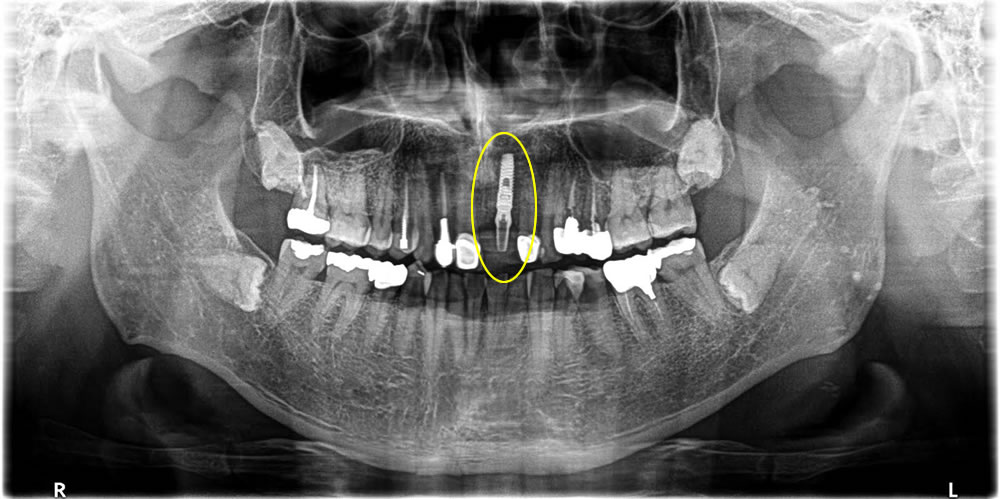

2週間後に糸を取り、4ヵ月置いてしっかりと骨とくっついている事を確認し、上部に歯を作っていきました。